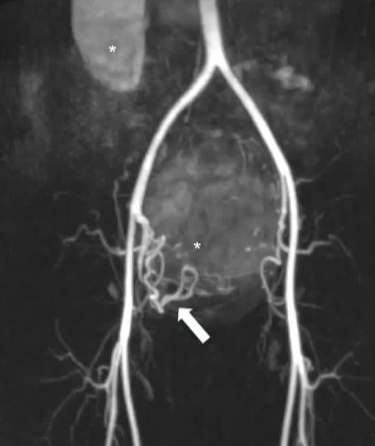

手术通过左侧桡动脉路径进行。 动脉造影显示右侧肾脏为单侧,右侧子宫动脉为单支,且左侧未发育的子宫角未获得明显的动脉供血。 通过一根微导管,使用直径为 500 - 700 微米的标定微球对右侧子宫动脉进行了栓塞,直至达到“修剪后的树状”终点位置。患者当天就出院了。 在三个月的随访中,患者表示所有症状都有所改善。